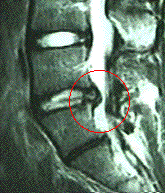

この図はMRと呼ばれる検査結果です。これは人間を縦切りにスライスしたある断面を横から見たものです。画面の右側が背中側、左がお腹側です。丸印の部分が椎間板が後方に脱出して神経を圧迫している様子を示しています。 またこの椎間板だけ色が黒く変性していることがわかります。